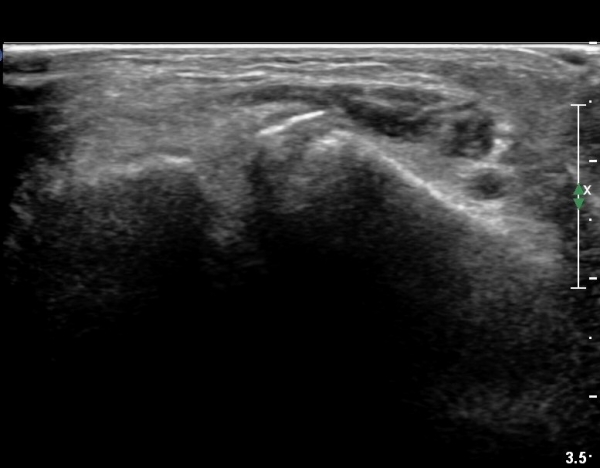

she revealed limping gait. on examination, there is swelling around ankle with limited ankle motion, localized tenderness at distal tibiofibular ligament and ATF ligament.

ÃÊÀ½ÆÄ °Ë»ç

CT : avulsion fracture of distal tibia at distal tibiofibulat ligament insertion.